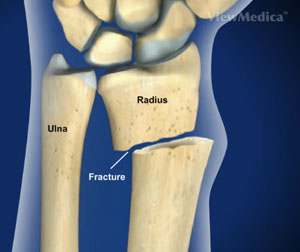

Pourazowy zespół cieśni nadgarstka występuje najczęściej jako powikłanie urazu ze złamaniem Colles'a lub jako powikłanie przebytego złamania w obrębie kości nadgarstka, zwłaszcza przebiegającego z przemieszczeniem odłamów, rzadziej jako powikłanie nieprawidłowego gojenia po przebytym urazie lub złamaniu tej okolicy. Zespół pourazowy może mieć przebieg ostry podczas gdy neuropatie na innym tle mają charakter przewlekły postępujący.

Złamanie nadgarstka